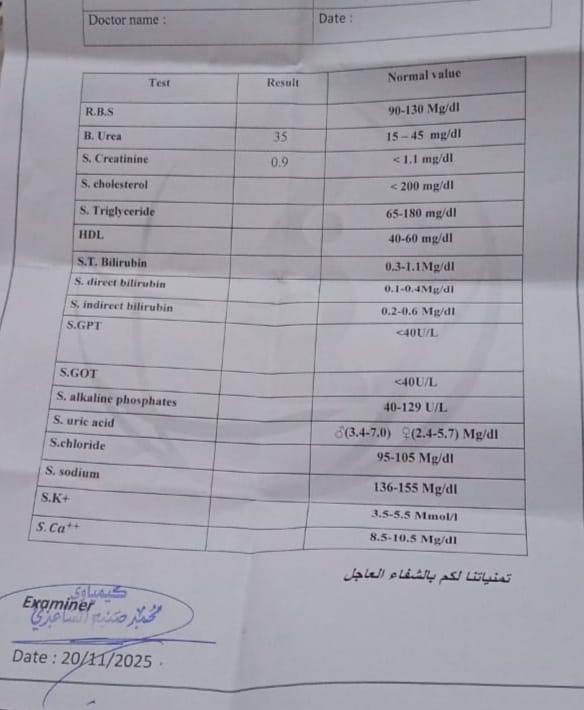

المريض، وهو من إحدى محافظات الجنوب العزيزة، كان يعاني من ارتفاع ضغط الدم والسكري، وتفاقمت حالته الصحية إلى أن وصلت مستويات اليوريا إلى 200 mg/dl و الكرياتينين إلى 12 mg/dl. وبعد تقييم دقيق في مستشفى الإمام الحجة (عج) الخيري، تبيّن أن السبب الحقيقي وراء تدهور وظائف الكلى هو تضخم غدة البروستات الذي أدى إلى انسداد الحالبين وتوسع الكليتين وصولًا إلى الفشل الكلوي.

وبفضل الله تعالى أولًا، ثم بمهارة الفريق الطبي، تجاوز المريض المرحلة الحرجة واستعاد وظائف كليتيه وتحسنت حالته بشكل كامل، ليغادر المستشفى معافى وقد طُويت صفحة الألم التي أثقلت عليه طويلًا.